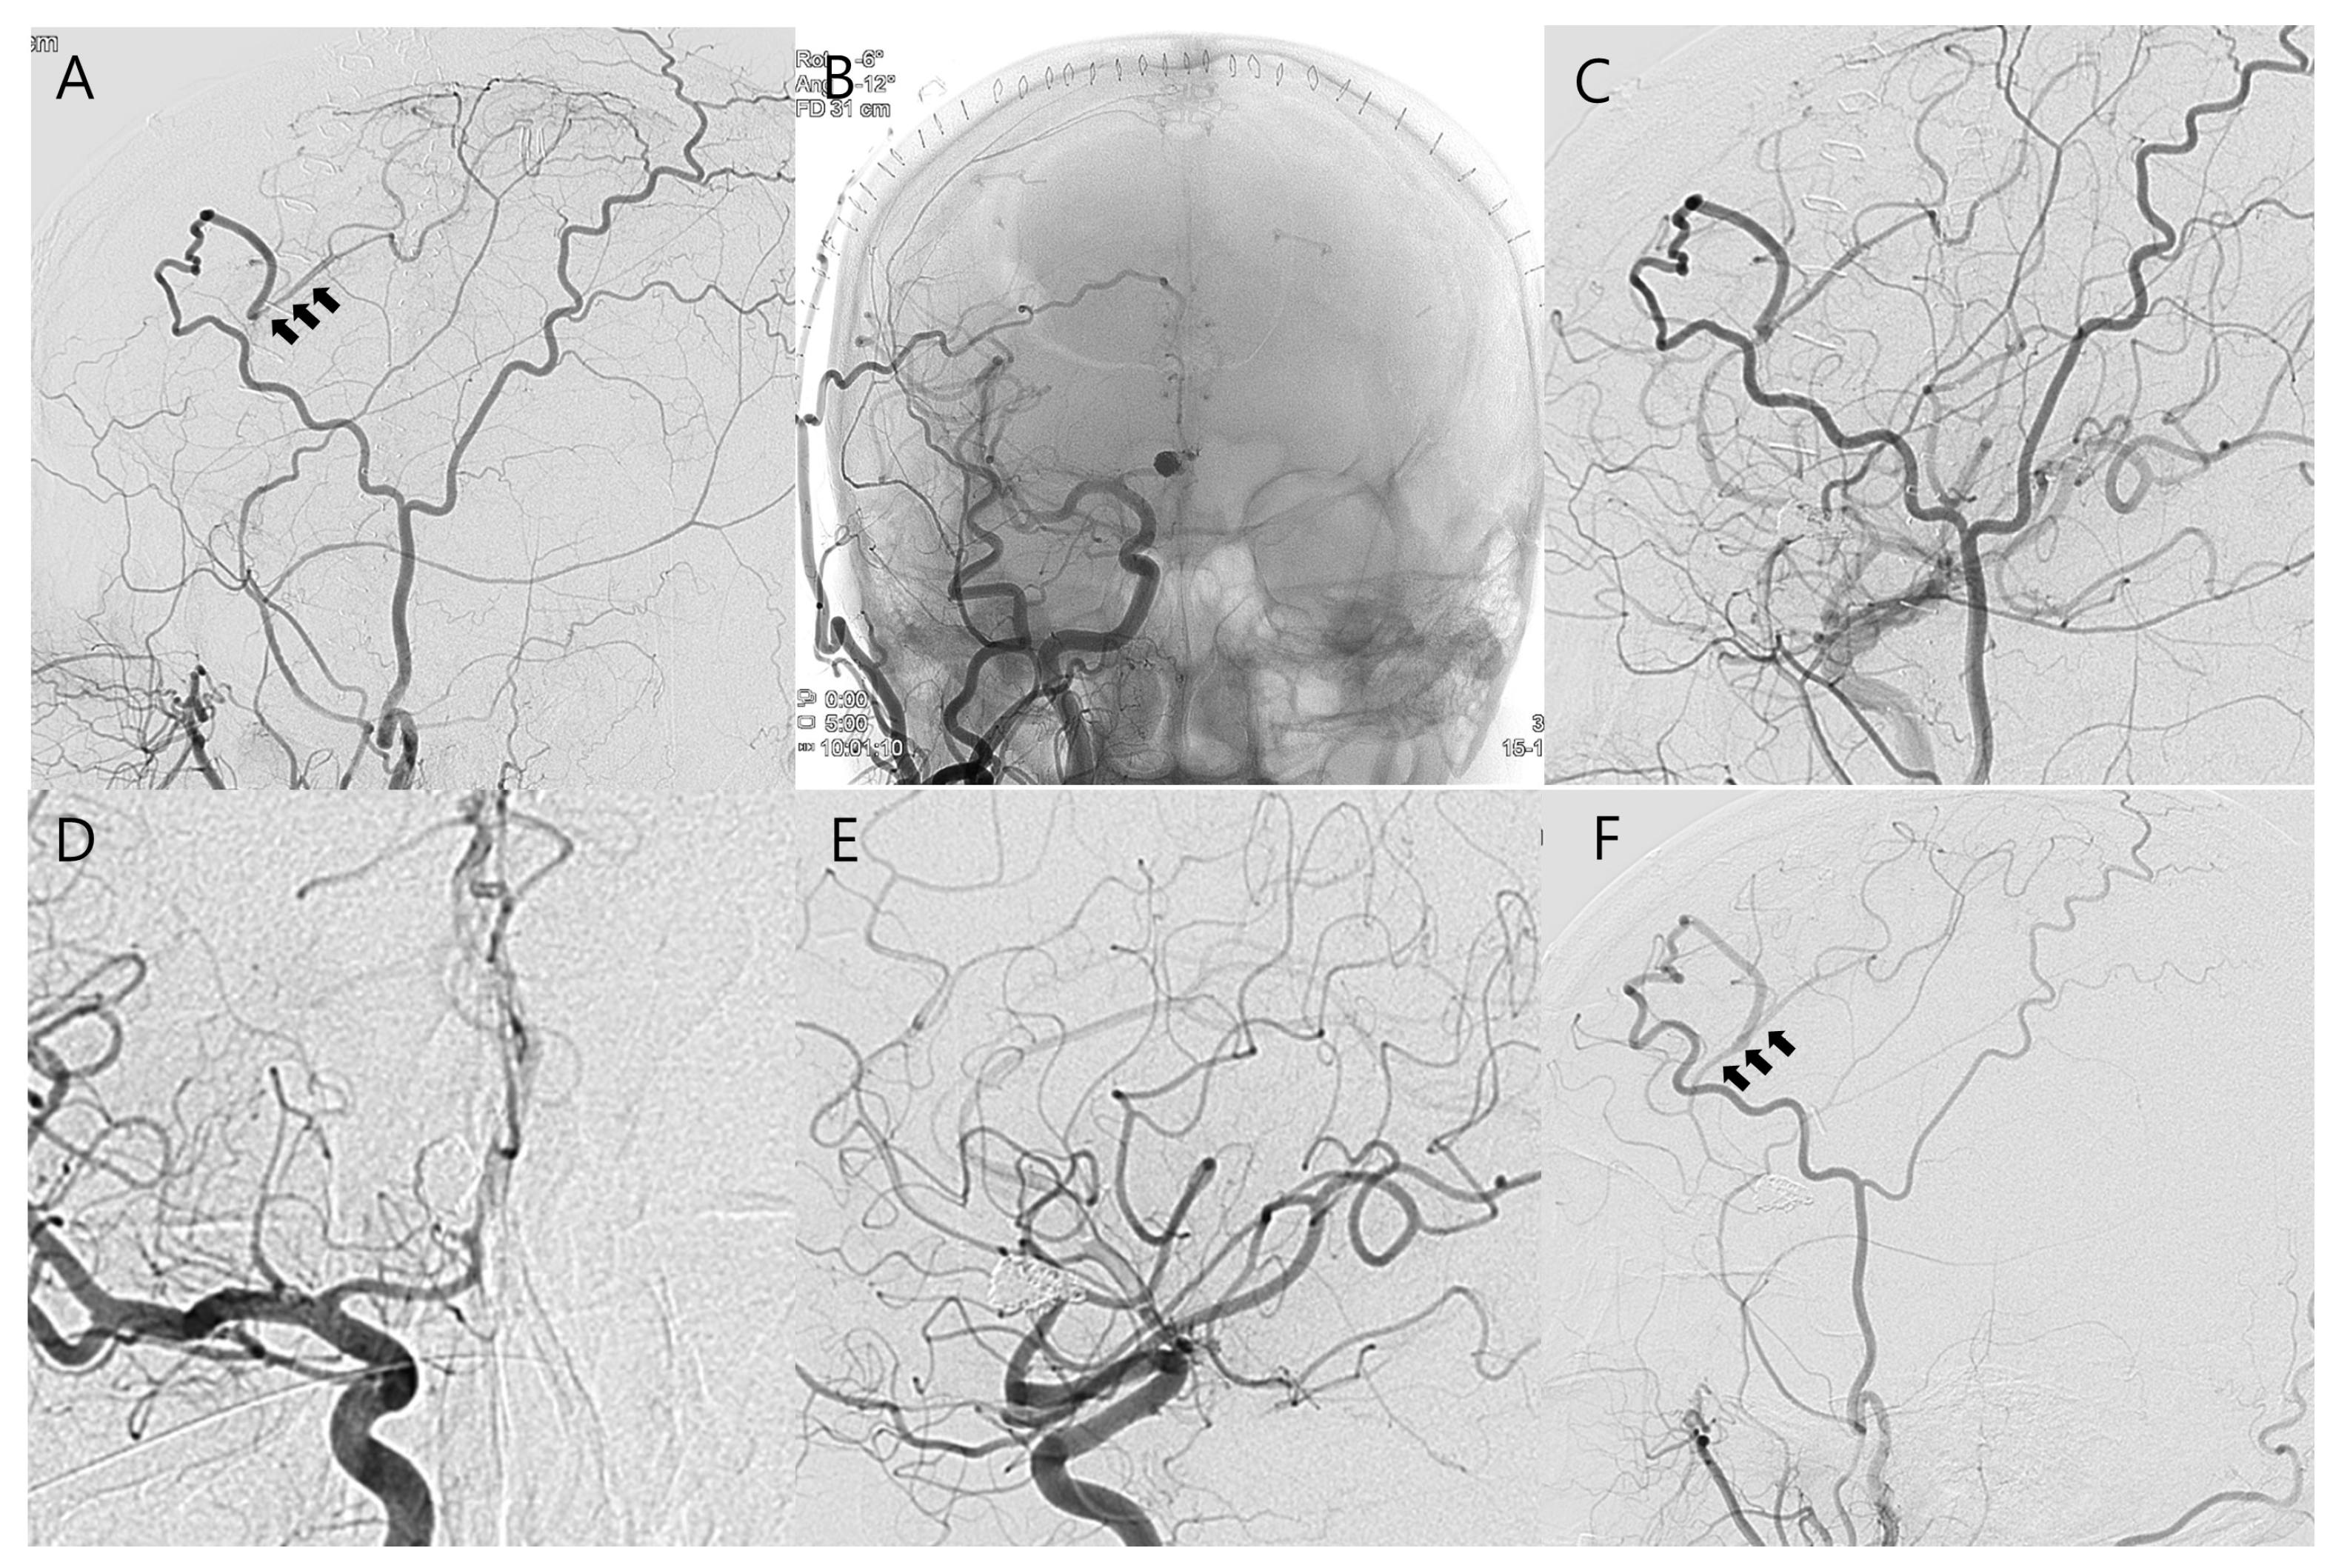

Combined Treatment of Large Fusiform A2 Aneurysm with End-to-Side Extended Superficial Temporal Artery–A3 Bypass Using Contralateral Superficial Temporal Artery Interposition Graft and Endovascular Aneurysm Trapping: A Case Report and Literature Review

2. Case Presentation

Kim, Y.-S.; Kim, J.-W.; Kim, W.-B.; Baek, B.-H.; Yoon, W.; Kim, T.-S.; Joo, S.-P. Combined Treatment of Large Fusiform A2 Aneurysm with End-to-Side Extended Superficial Temporal Artery–A3 Bypass Using Contralateral Superficial Temporal Artery Interposition Graft and Endovascular Aneurysm Trapping: A Case Report and Literature Review. J. Clin. Med. 2025, 14, 2927. https://doi.org/10.3390/jcm14092927